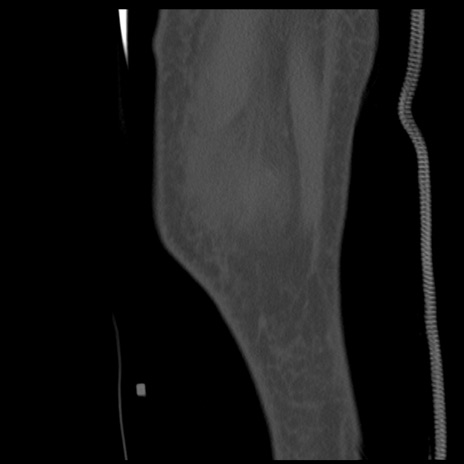

症例28 右膝関節CT(矢状断像)

右膝関節CT